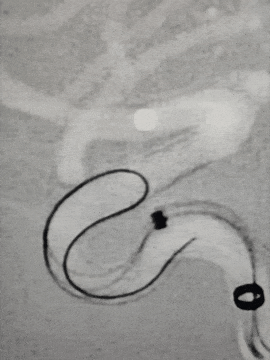

退支架外鞘管,将Surpass Streamline血流导向密网支架先释放到CAT5里6-7mm。

再退CAT5到外鞘管以下2mm,让支架锚定于远端。但发现支架远端定位过高,覆盖了脉前动脉,遂用CAT5回收支架,重新定位后释放。

由于血管迂曲,支架推出困难,遂进行远端减张释放,推出支架后再增张,因此导致支架远端打开不良,用3.5*15mm Gateway球囊在支架远端扩张。

球囊扩张后再进行导丝按摩支架,工作位造影显示支架贴壁有所改善,动脉瘤内造影剂滞留明显。